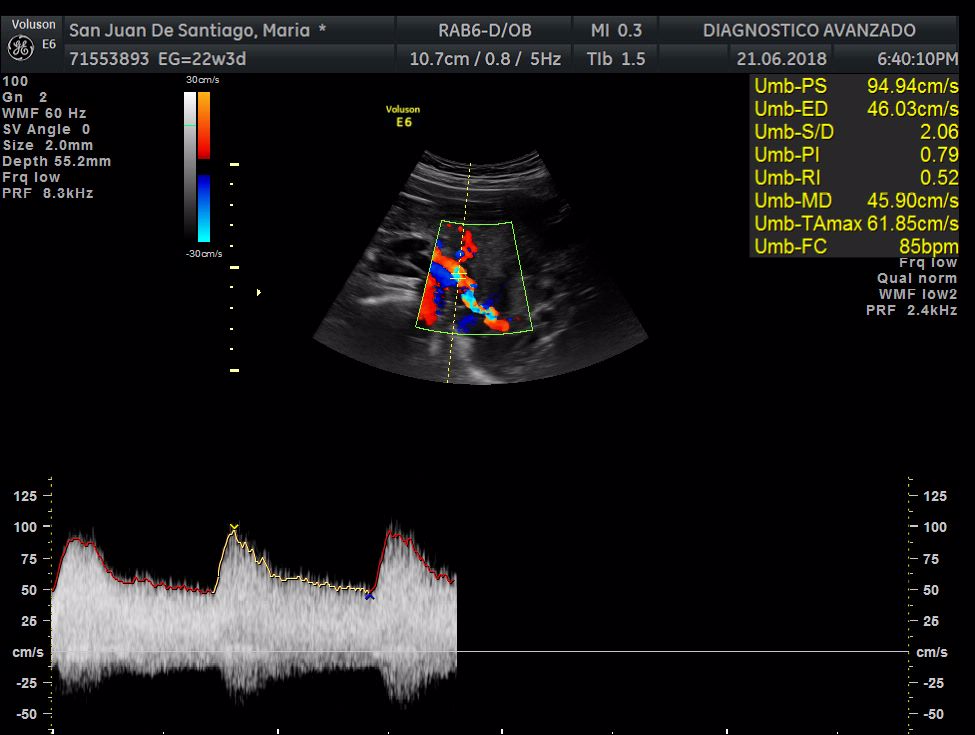

¡Hola a todos! Hoy hemos ido a hacer la tradicional ecografía 3D de la niña, os dejamos todo el material (aunque es un poco demasiado).